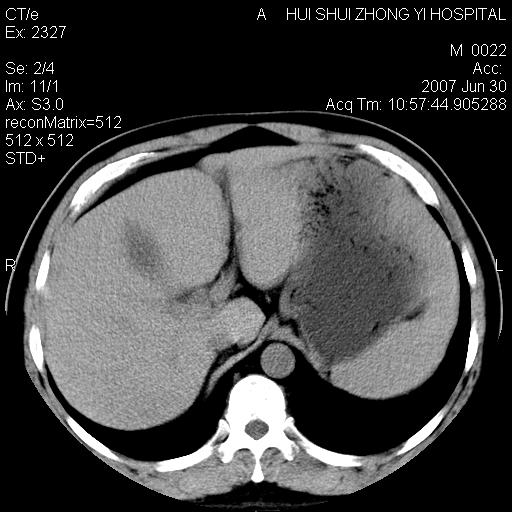

肝右叶密度减低区?

支持双肾结石,肝右叶低密度影为胆囊部分容积效应。

肝右叶低密度影为胆囊部分容积效应?为什么s43.0层面下来不见胆囊影,而是相隔了一层才见胆囊影。这是按我们扫描的顺序发的,但是是追加扫描的。

肝右叶低密度灶,增强!

支持双肾结石,肝右叶低密度影为胆囊部分容积效应

病人呼吸动了,第四层应该在第五\\六层之间。肝右叶低密度影为胆囊部分容积效应。双肾结石。

病人呼吸运动了

不连续,是呼吸造成的。

双肾结石,肝右叶低密度影为胆囊部分容积效应。

考虑:1、水平肝;